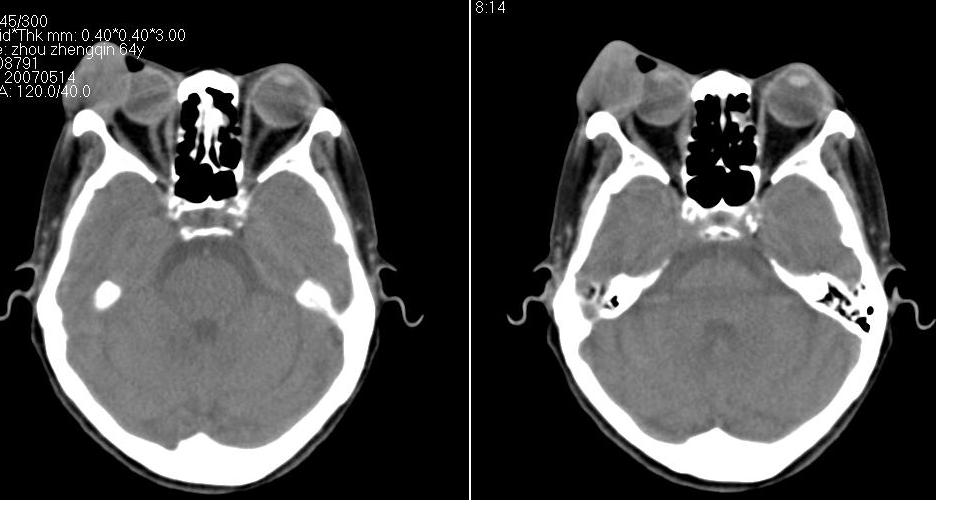

以下是引用zhw974247在2007-5-14 19:34:00的发言:[br]泪腺肿瘤在眶原发性肿瘤中发病率最高,而泪腺混合瘤又是其中最常见者,有良性及恶性二种。良性泪腺混合瘤多见于中年人,病程长,来源于泪腺管或腺泡,也可以起源于副泪腺及先天性胚胎组织残留(泪腺原基)。恶性泪腺混合瘤缺少或无完整的包膜,肿块与眶缘发生粘连,粘连部眶缘有压痛。瘤组织除有良性泪腺混合瘤的结构外,还有癌变的组织构成。瘤组织向眶内浸润,破坏骨质,可发生全身转移,严重者向颅内转移,危及生命。[br]